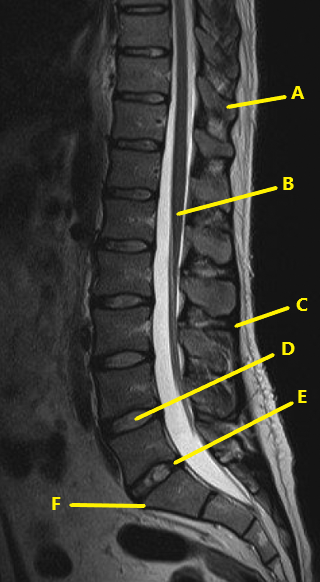

What letter is the intervertebral disc at L2-3 ?

C

What is letter D ?

nucleus pulposis

What is letter E ?

annulus fibrosis